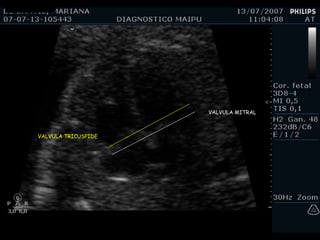

EXAMEN BASICO VALVULAS AV Apertura y movimiento Inserción

VALVULA MITRAL VALVULA TRICUSPIDE